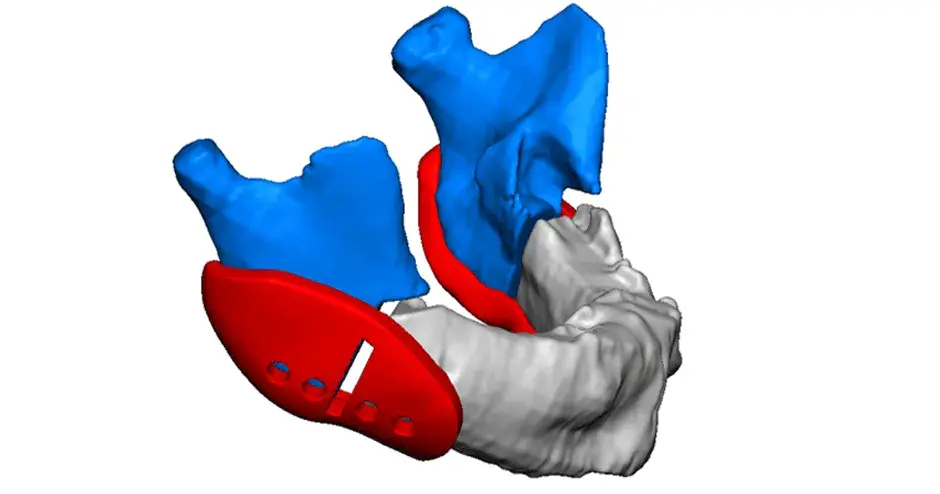

3D Systems' VSP® surgical planning solutions for craniomaxillofacial (CMF) applications received FDA clearance as a service-based approach to personalized surgery over 10 years ago.

3D Systems and Stryker Corporation have partnered to provide surgeons with best-in-class products and services for craniomaxillofacial surgeries. As a leader in personalized healthcare solutions, 3D Systems has planned and delivered devices for more than 140,000 patient-specific cases. The Stryker Craniomaxillofacial business specializes in providing patient-specific options and innovative solutions that help drive efficiencies in surgical suites. The combination of Stryker’s specialized team and advanced implants with 3D Systems' cutting-edge 3D printing technologies and expert consulting services positions both companies to provide a superior level of service to healthcare professionals who use these revolutionary solutions.